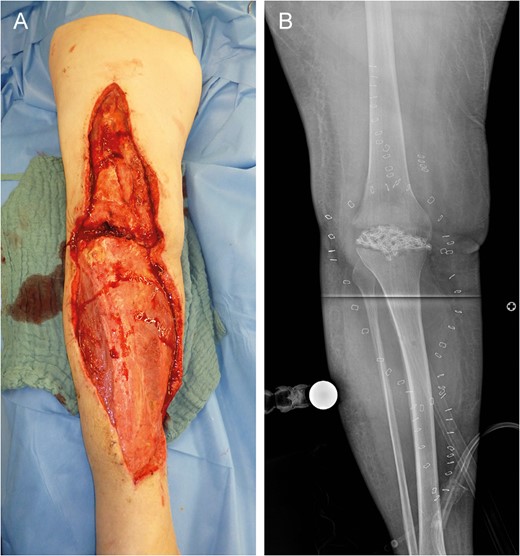

Left lower limb tissue defect on admission (A) and corresponding X-ray (B).